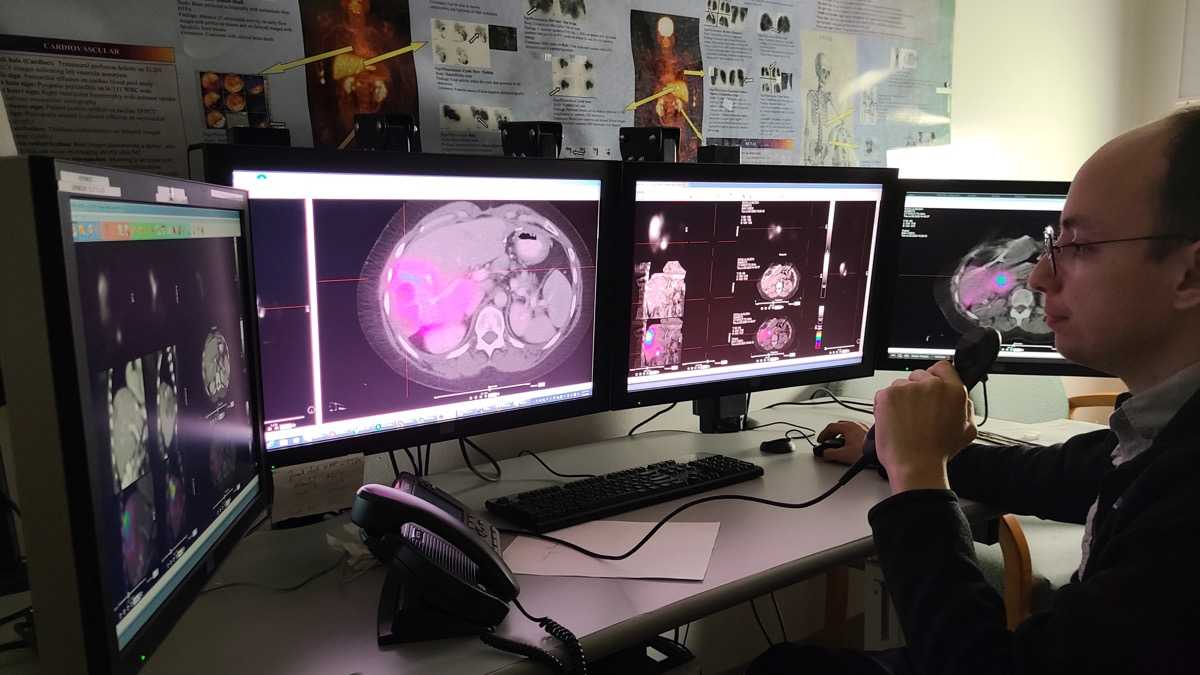

We prepare our residents for their careers as physicians with a training that emphasizes hands-on teaching and graded independence. Our Diagnostic Radiology Residents learn to dictate cases independently through apprentice-style teaching at the workstation and an extensive didactic teaching curriculum, while our Integrated Interventional Radiology Residents gain valuable clinical experience by practicing in multiple environments and managing patient care. Each resident sees a high volume of cases, including severe cases in our NCI Cancer Center and Liver Transplant Program. Specialty collaboration, direct feedback, collegiality and research opportunities allow every resident to maximize their potential.

An academic hospital adjacent to our Albert Einstein College of Medicine

On the East Campus, the Jack D. Weiler Hospital is the central hub where Montefiore Einstein Radiology Residents experience hands-on training in an academic community hospital setting. The hospital’s location at the Albert Einstein College of Medicine Campus allows fellows to work directly with faculty and develop independence through hands-on-training. Weiler is also home to the Albert Einstein Cancer Center, which provides extensive case material for clinical cases and highlights multiple interdisciplinary conferences. Residents work directly with faculty on the Interventional Radiology (IR) service and take independent calls as senior residents from Einstein, enhancing their learning and independent clinical practice. The East Campus is also home to the PET Imaging Center, a dedicated Nuclear Medicine outpatient facility, and the nearby Comprehensive Breast Cancer Care Center.

Department of Radiology Fellowship Programs

Montefiore Einstein Radiology offers competitive fellowship programs in numerous clinical areas. Our mix of ACGME-accredited and non-accredited programs benefits from a long-standing history of academic excellence. Fellows are exposed to state-of-the-art technology, groundbreaking research and a wide range of cases, and have access to sub-specialized leaders who help advance the field of imaging.